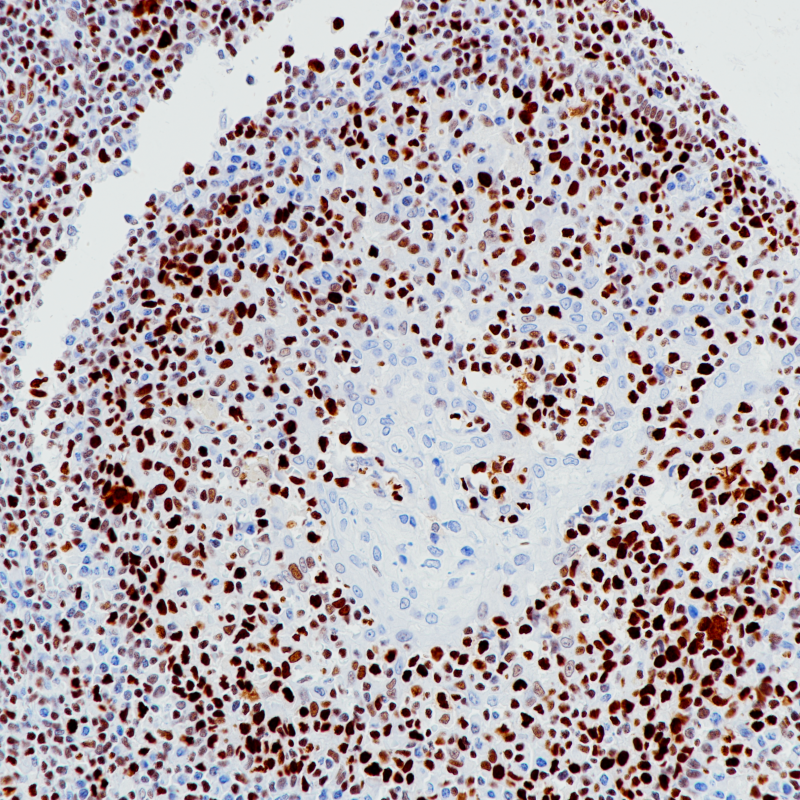

扁桃体MCM2(BP6220)染色

MCM2作为MCM2-7复合体的组成部分,在耳蜗毛细胞的终分化发育中发挥作用,并诱导细胞凋亡。MCM2在所有增殖细胞中均有表达。作为一种特殊的细胞增殖标志物,在结肠癌、肺癌等上皮组织的癌前病变中优于Ki-67。它有助于恶性间皮瘤和反应性间皮瘤的研究。

细胞核